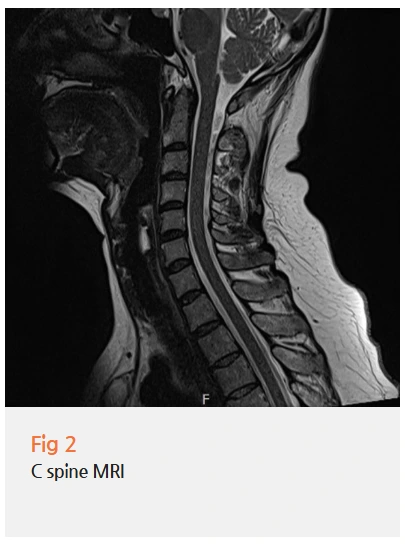

그래서 당일 MRI 검사를 진행했죠.

MRI 검사 결과 경추 3-4번, 요추 4-5번에서

추간판 퇴행성 변화와 경미한 신경 압박 소견이 관찰됐습니다.

단독으로는 큰 문제가 아닐 수 있지만,

이게 자율신경계 기능 저하와 결합되면서

전신적인 이상 감각을 유발하고 있었던 거예요.